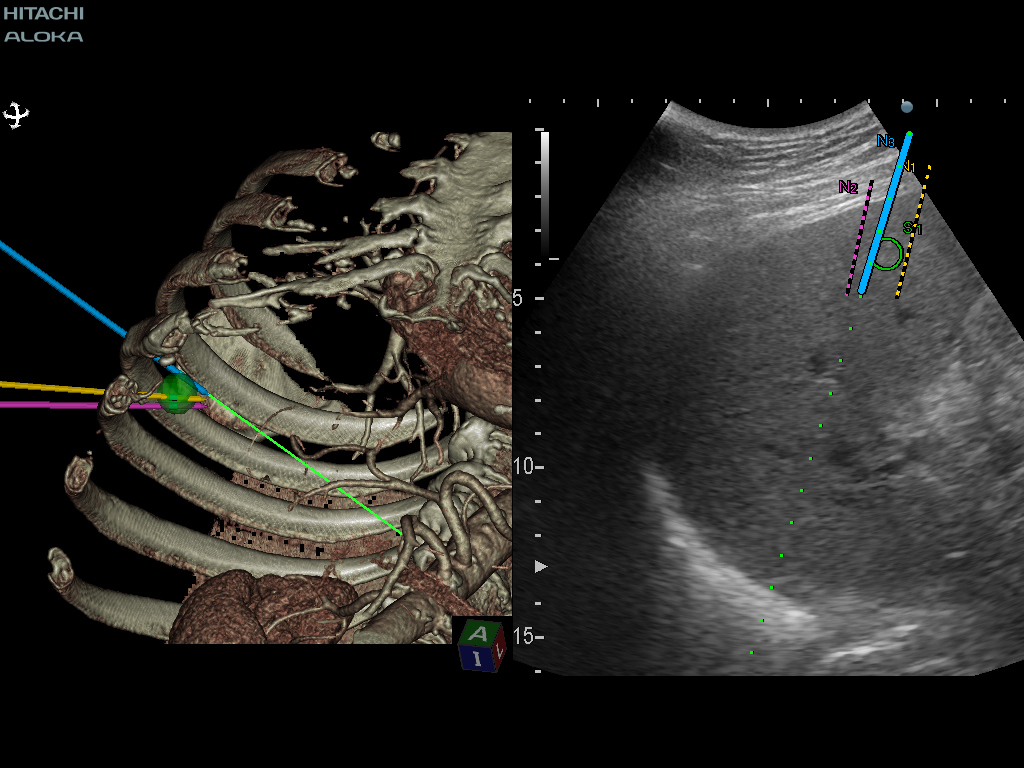

생검 계획 및 중재 적 지원을 위해 표시된 목표 경로와 바늘 경로 사이의 위치 관계.

태아의 뇌 검사에서 실시간 가상 초음파 검사 (RVS)는 중뇌의 형성 (예 : pons and tegmentum), 특히 측두엽의 회전과 같은 특정 해부학 적 특징을 인식하는 데 도움이 될 수 있습니다.